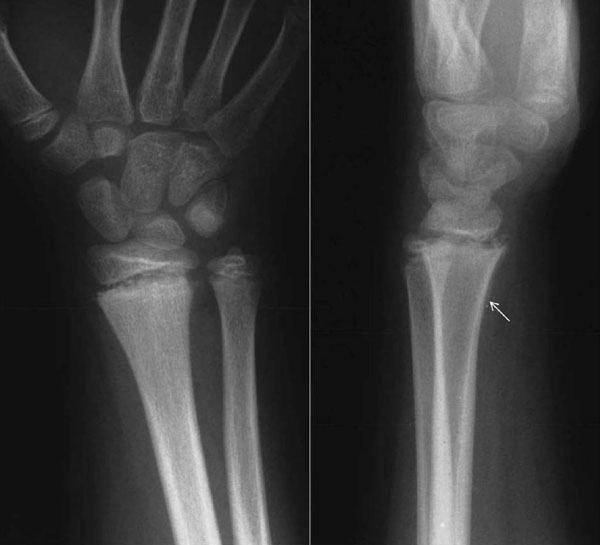

Fig. (1) A 10-year-old boy forced his wrist into full extension while playing football. Clinical examination was indicative of a physeal fracture of the distal radius. The radiographs were negative. He was treated with a splint. Radiographs 5 weeks post-injury indicated a Salter-Harris type II lesion. The findings included widening of the distal radial physis on both views, widening between the palmar metaphyseal flake fragment and the metaphysis on the lateral view, and periosteal reaction on the palmar aspect of the radius (arrow).